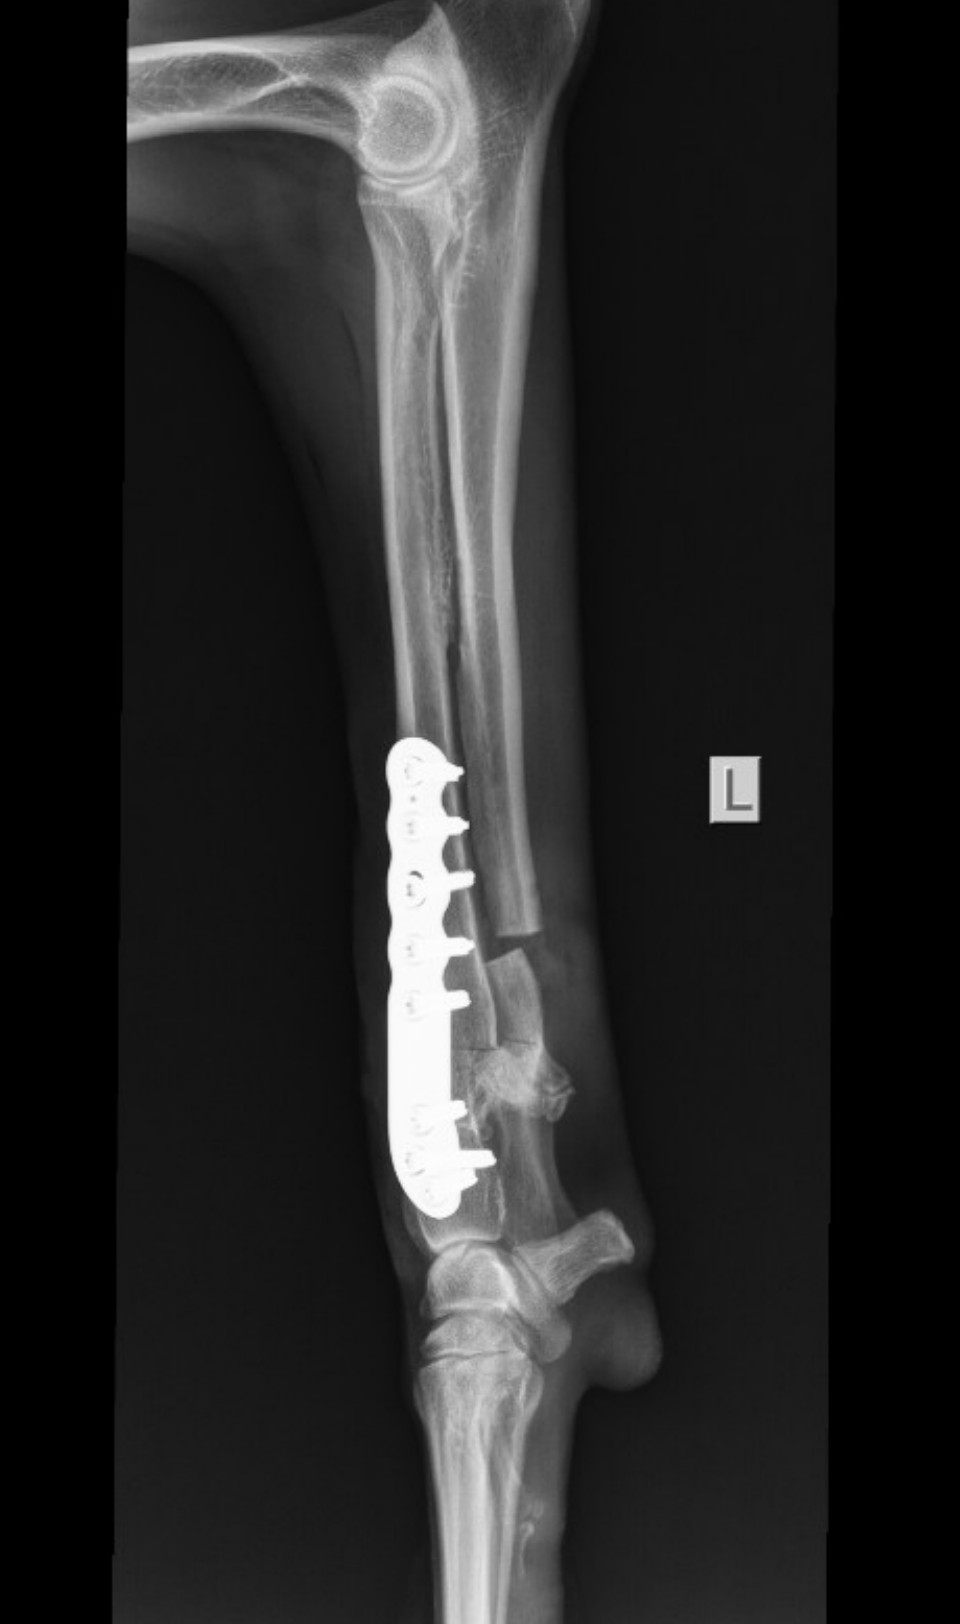

Im Refugio abgegeben, weil er nicht länger zu gebrauchen war: Joselito hat seinem Besitzer treu gedient, war schnell und gehorsam. Doch dann verletzte er sich bei der Jagd und brach sich das linke Vorderbein.

Ein Besuch beim Tierarzt kam für den Jäger nicht infrage. Viel zu teuer! Mehrere Wochen versuchte Joselito unter großen Schmerzen, weiter nützlich zu sein, doch mit dem unbehandelten Bruch konnte er nicht mehr rennen.

Die Tierärztin wollte den Bruch nicht mehr operieren, weil sich bereits ein Callus gebildet hatte und sie den Knochen erneut hätte brechen müssen. Und Joselito war weiterhin tapfer.

Nach einigen Untersuchungen in der Tierklinik stand fest, dass eine OP unumgänglich sei. Joselito kam unters Messer, und dabei wurde festgestellt, dass es um sein Bein weit schlimmer stand als befürchtet. Schon die erste OP hat knapp viertausend Euro verschlungen, und es werden noch zwei weitere benötigt, damit Joselito endlich wieder schmerzfrei durchs Leben gehen kann.